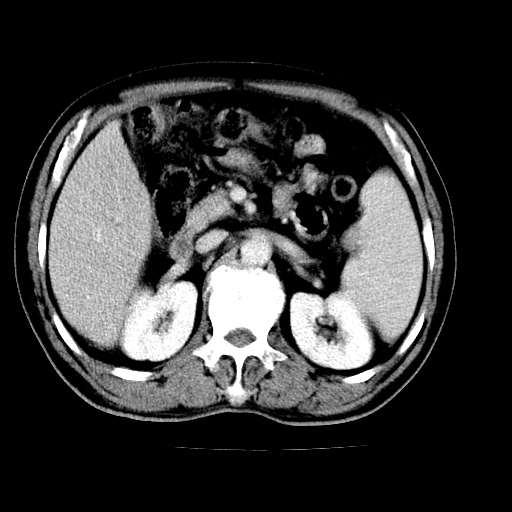

男,66岁,上腹部不适、黄染一周。彩超示:肝左叶占位,肝内胆管扩张,胆总管扩张,胆总管占位?

肝左叶占位性病变,并胆管扩张,符合胆管细胞癌ct表现,门脉左支受累,左肾囊肿。窗宽太窄了,其他的看不清

左叶胆管细胞癌累及胆总管,门脉左支受侵,慢性胆囊炎胆结石,左肾小囊肿